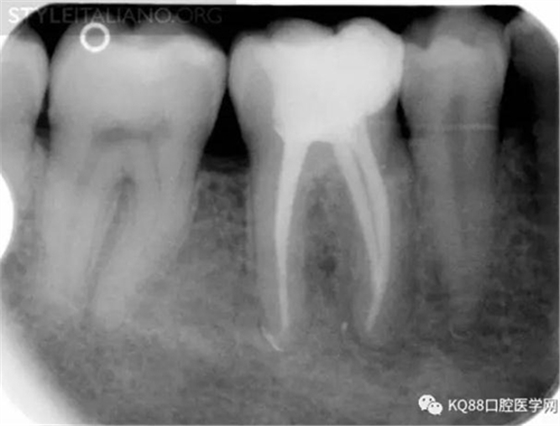

Case 1: In this patient, persistent pain was present after endodontic treatment of a vital tooth. The periapical x-ray showed an inadequate shaping of the distal root canal, regarding both the working length and the apical taper.

Img. 2 - Retreatment of distal canal was performed using ProTaper retreatment files. Working length was assessed electronically. Canal was shaped with a Reciproc R40, thoroughly irrigated with US activation, filled with corresponding Guttafusion obturator. Pain disappeared completely some days after retreatment. In all likelihood, incomplete preparation allowed residual pulp tissue to remain in the root canal, acting as an irritant.